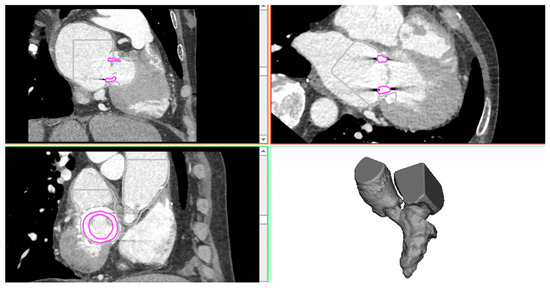

Figure 1.

CTA images showing the axial, sagittal, and coronal view as well as the 3D heart anatomy after segmentation.